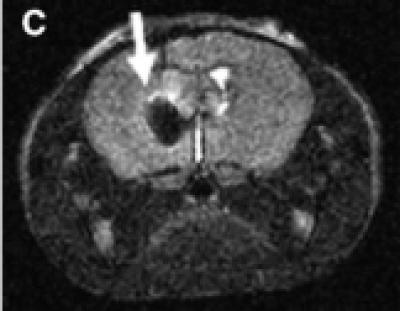

The antibody-linked particles lengthened survival of the tumor-implanted mice: their median survival was 19 days compared to 16 days for bare particles and 11 days for no particles. The particles also made the tumor visible via MRI, darkening the area of the brain where the tumor is (see accompanying image). Hui Mao, PhD associate professor of radiology, and his team of researchers, contributed MRI experiments showing the sensitive imaging qualities of the iron-oxide nanoparticles in vitro and in the mouse brain.